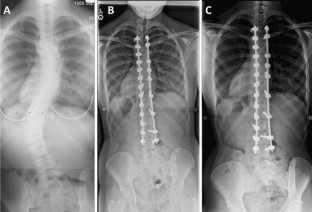

Fig. 1

Fig. 2